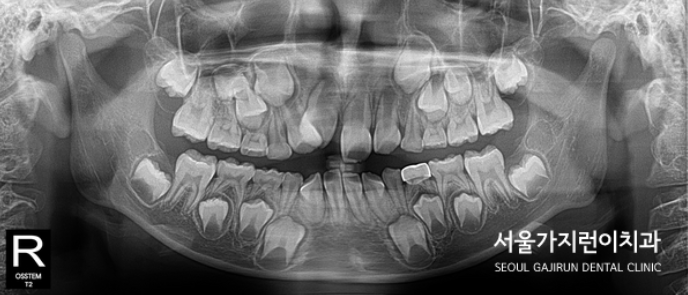

겉으로 보이지는 않지만 성장기에는 숨어있는 치아들이 보이는데요. 잇몸 위로 숨어있는 치아들이 유치들이 빠지고 뒤이어 나올 영구치인 것을 볼 때 치아배열에 문제가 생겼을 때 2차 교정을 시작할 수 있으니 그 전에 예방교정으로 프리올소를 통해 맹출하는 치아들이 제대로 자리 잡을 수 있도록 교정해볼 수 있겠습니다.